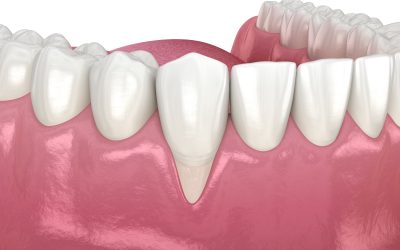

Cisti dentale: cause e sintomi

La cisti dentale è una formazione patologica che si sviluppa generalmente all’apice di un dente a seguito di un’infezione non trattata. Si presenta come una cavità contenente liquido, delimitata da una membrana, e può rimanere asintomatica oppure causare dolore, gonfiore e complicanze più gravi. Nella maggior parte dei casi deriva dalla necrosi della polpa dentale, spesso causata da carie profonde, che inizialmente provocano pulpiti e successivamente la morte del nervo. Se non curato, il granuloma che si forma all’apice del dente può evolvere in una vera e propria cisti, arrivando anche a compromettere la sopravvivenza del dente interessato.